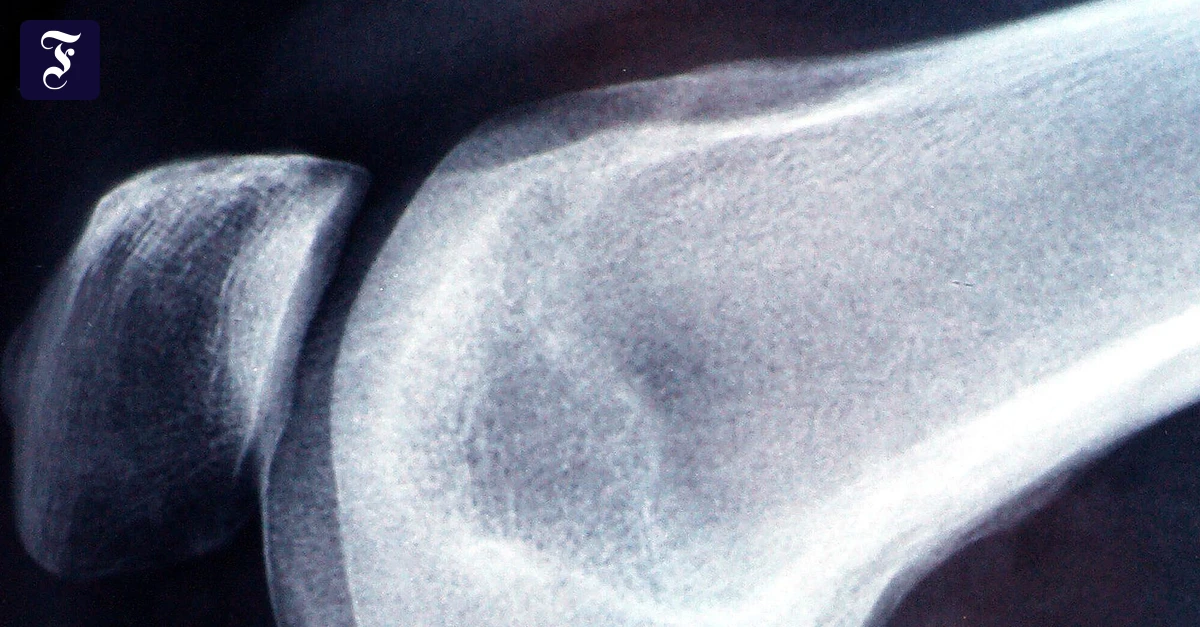

Neue Hüfte, neues Knie: High-Tech-Verfahren versprechen höhere Präzision und mehr Sicherheit beim Gelenkersatz. Aber auch die Patienten selbst können dazu beitragen, dass die Behandlung erfolgreich verläuft....weiterlesen »